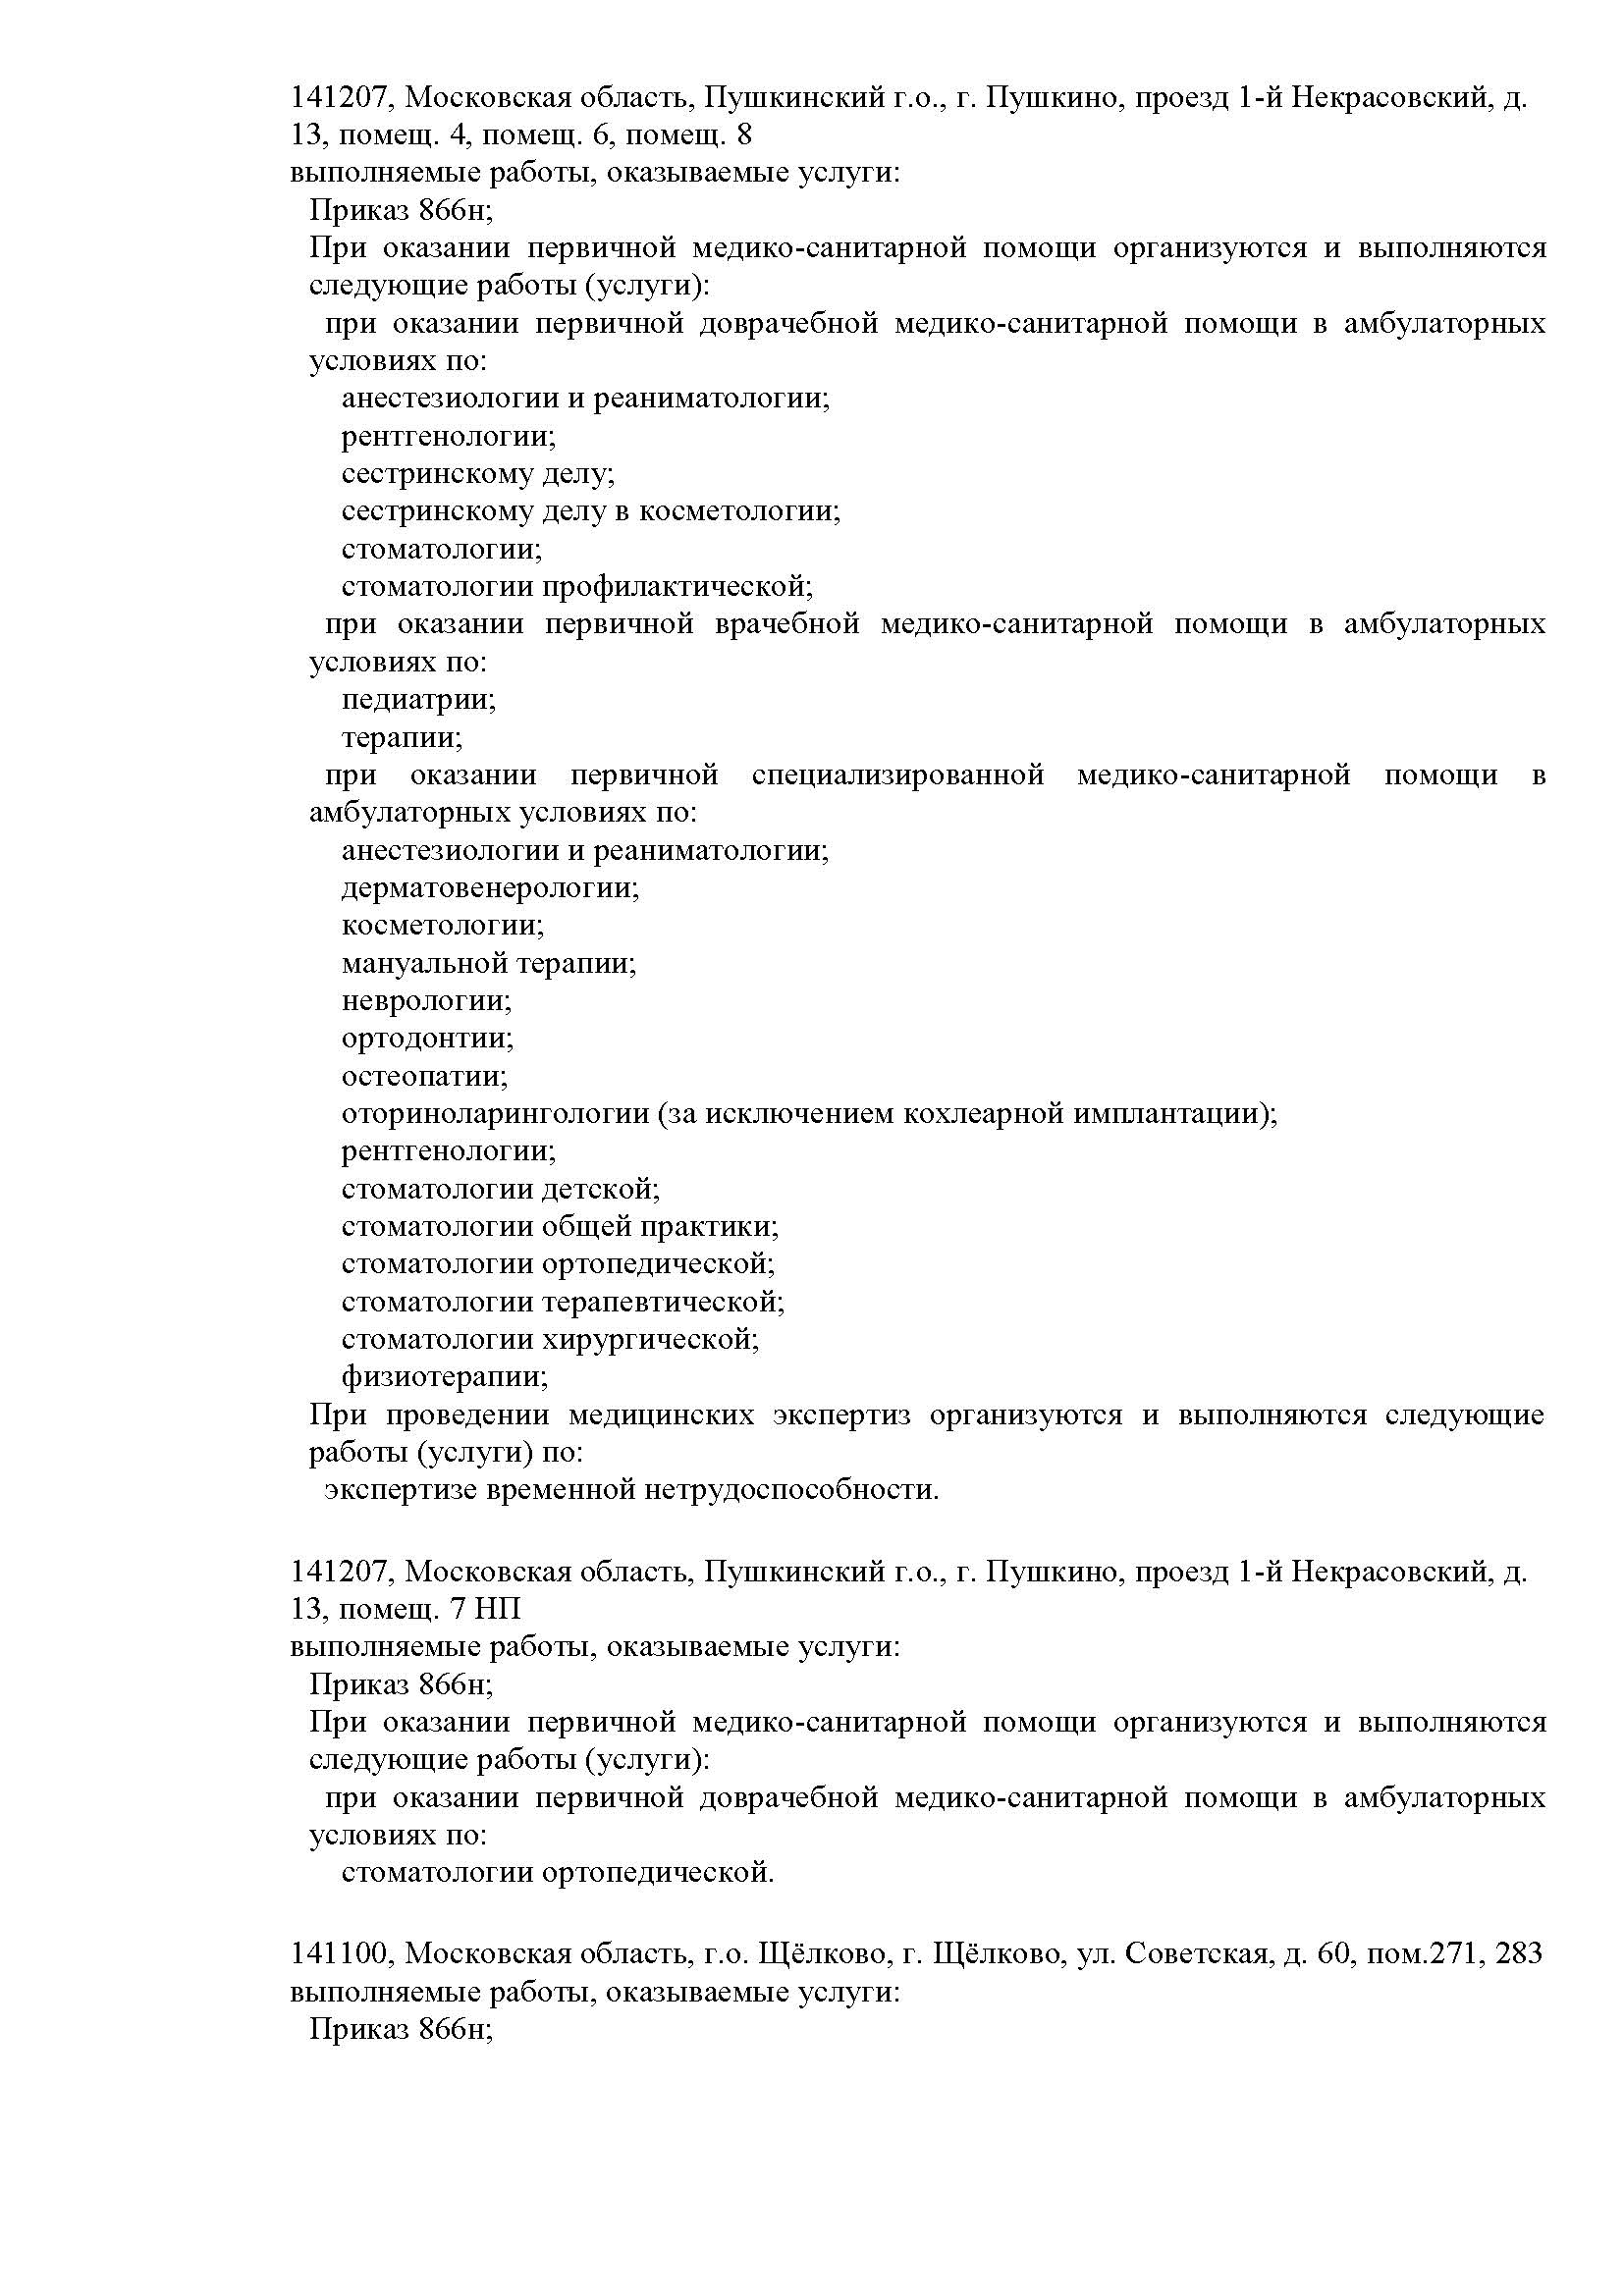

Наши лицензии